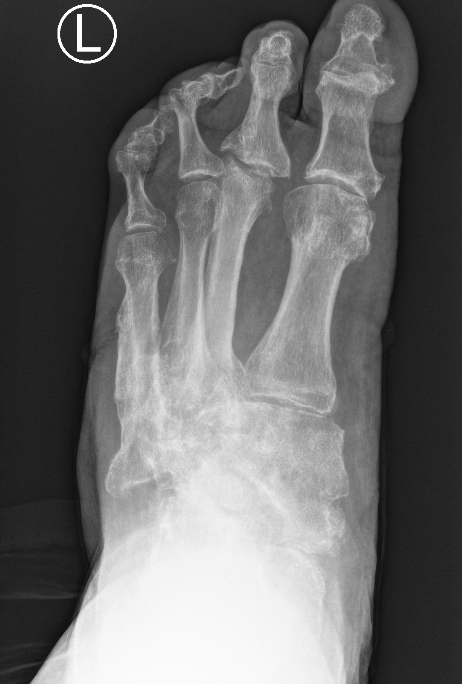

Midfoot dissolution, coalescence and reconstruction

Xray

Midfoot collapse

Midfoot collapse and rocker bottom foot with small ulcer

Midfoot collapse with subluxation of midtarsal joints